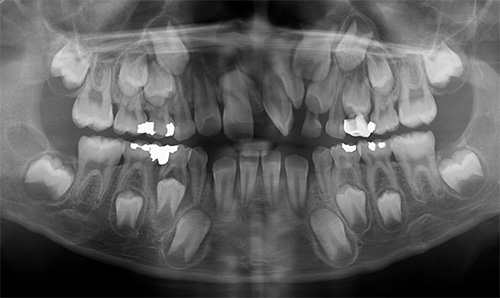

Orthodontic Treatment X-ray - Before

After Series of Teeth Extractions, Upper Left Canine Unerupted.

Ready to Start Ortho Treatment

Orthodontic Treatment X-ray - After